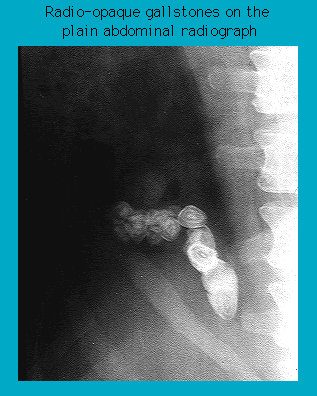

Radiograph showing radio-opaque gallstones